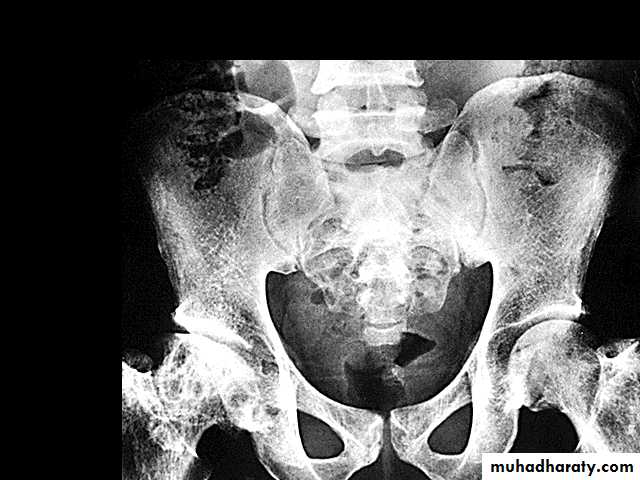

Sickle cell crisis.1.Splenic crisis (splenic sequestration syndrome,auto splenectomy)2.Infections.3.CNS and ophthalmic events (CVA, proliferativeretinopathy).4.Acute chest syndrome (chromic pulmonary hypertension lead to cor-pulmonale).5.GIT : diffuse abdominal Pain.6.Genitourinary symptoms:- Painless haematuria.- hyposthenuia.- priapism.- hypogonadism.Sickle cell crisis Cont.7.skeletal complication

- hand-foot syndrome.acute arthritis.aseptic necrosis of the head of femur.osteomyelitis .8.Skin changes lead to chronic non-healing ulcer